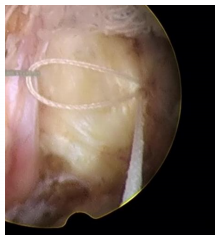

一次性纖維環(huán)縫合器的臨床應(yīng)用:

隨著纖維環(huán)縫合器縫合纖維環(huán)技術(shù)的推廣,很多學(xué)者做了相關(guān)的臨床研究。Parker等對(duì)30例纖維環(huán)縫合患者進(jìn)行了2年隨訪研究,零復(fù)發(fā)且椎間隙高度無(wú)改變。Bailey等通過對(duì)750名患者對(duì)比研究,發(fā)現(xiàn)纖維環(huán)非縫合組在術(shù)后2年時(shí)的再手術(shù)率較縫合組高45%。研究發(fā)現(xiàn),縫合纖維環(huán)可提高椎間盤生物力學(xué)性能,縮短其愈合時(shí)間,同時(shí)也減緩椎間盤組織的退變進(jìn)程。修復(fù)后纖維環(huán)回縮可減少對(duì)神經(jīng)根刺激,可有效消除疼痛癥狀。目前LDH髓核摘除術(shù)后復(fù)發(fā)的主要病因?yàn)槔w維環(huán)缺損、持續(xù)重復(fù)應(yīng)力因素等,比較明確的病因?yàn)槭中g(shù)導(dǎo)致的纖維環(huán)缺損,總結(jié)得出髓核突出少、纖維環(huán)缺損嚴(yán)重者術(shù)后的復(fù)發(fā)率高??p合后纖維細(xì)胞受到反復(fù)牽拉應(yīng)力刺激,可促進(jìn)纖維環(huán)的愈合和防止炎癥因子的產(chǎn)生。纖維環(huán)愈合產(chǎn)生的瘢痕組織可減輕關(guān)節(jié)突關(guān)節(jié)的應(yīng)力作用。縫合纖維環(huán)可提高術(shù)后髓核“再水化”,促進(jìn)腰椎功能恢復(fù)。纖維環(huán)縫合益處:閉合裂口;降低術(shù)后復(fù)發(fā)率及再手術(shù)率;減輕髓核組織的免疫學(xué)反應(yīng)和炎癥介質(zhì)的外滲;有利于髓核的再生修復(fù)。要點(diǎn):切口大小以5mm的線形縱切口較佳,8mm以上需平行或交叉縫合2針;縫合針距離邊緣2~3mm為宜;縫合前,應(yīng)行邊緣探查,尋求無(wú)佳的縫合點(diǎn)。目前纖維環(huán)縫合面臨的重要問題是如何改善或降低縫合處的應(yīng)力積累,受應(yīng)力積累影響瘢痕組織及神經(jīng)纖維可能侵入椎間盤,可引起盤源性疼痛。有學(xué)者對(duì)比研究得出,單針簡(jiǎn)單縫合,可降低術(shù)后復(fù)發(fā)率,雙針交叉或平行縫合療效更好,而改良荷包縫合,術(shù)后能避免髓核再次突出,生物力學(xué)完整性可得到更好保留。

一次性纖維環(huán)縫合器手術(shù)中注意事項(xiàng):

①適度增大開窗,便于縫合器的擺放及調(diào)整;

②切開纖維環(huán)時(shí)避免傷及內(nèi)側(cè)的神經(jīng)根及硬膜囊;

③摘除髓核時(shí),避免損傷切口兩側(cè)的纖維環(huán),盡量保留纖維環(huán)殘端的長(zhǎng)度和厚度以便于縫合;

④縫合時(shí),纖維環(huán)縫合器的扳機(jī)應(yīng)朝向術(shù)者對(duì)側(cè),避免因扳機(jī)遮擋影響術(shù)中穿刺;

⑤直針穿刺時(shí)旋鈕要旋轉(zhuǎn)到位,標(biāo)志線對(duì)齊,避免打成空結(jié);

6.?從纖維環(huán)切口的中1/3 處縱向縫合,避免縫線一側(cè)。